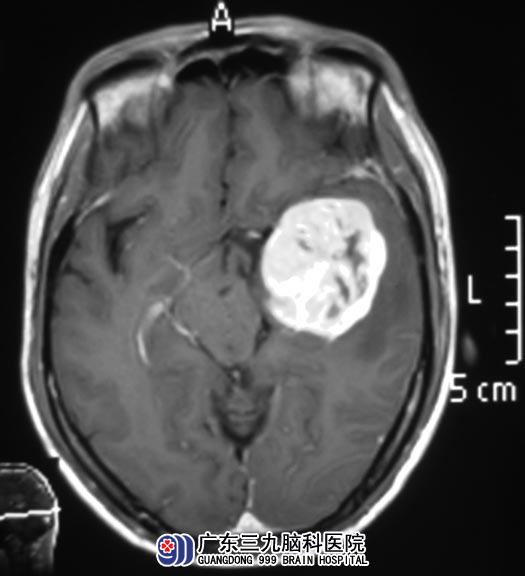

家人为了弄个明白,带着他去医院,头颅MR检查提示:左侧颞叶巨大占位性病变。

完成相关检查后,由广东三九脑科医院综合神经外科 鲁明主任主刀,在唤醒麻醉下行左侧颞叶占位切除术,显微镜下见颞叶脑组织膨胀,肿瘤与丘脑、中脑、桥脑粘连。在语言及肢体活动保护完好的情况下将肿瘤全切。术后叶先生的语言及肢体运动功能完好,记忆力、理解力都明显好转。病理结果为:胶质母细胞瘤(WHO IV级)。